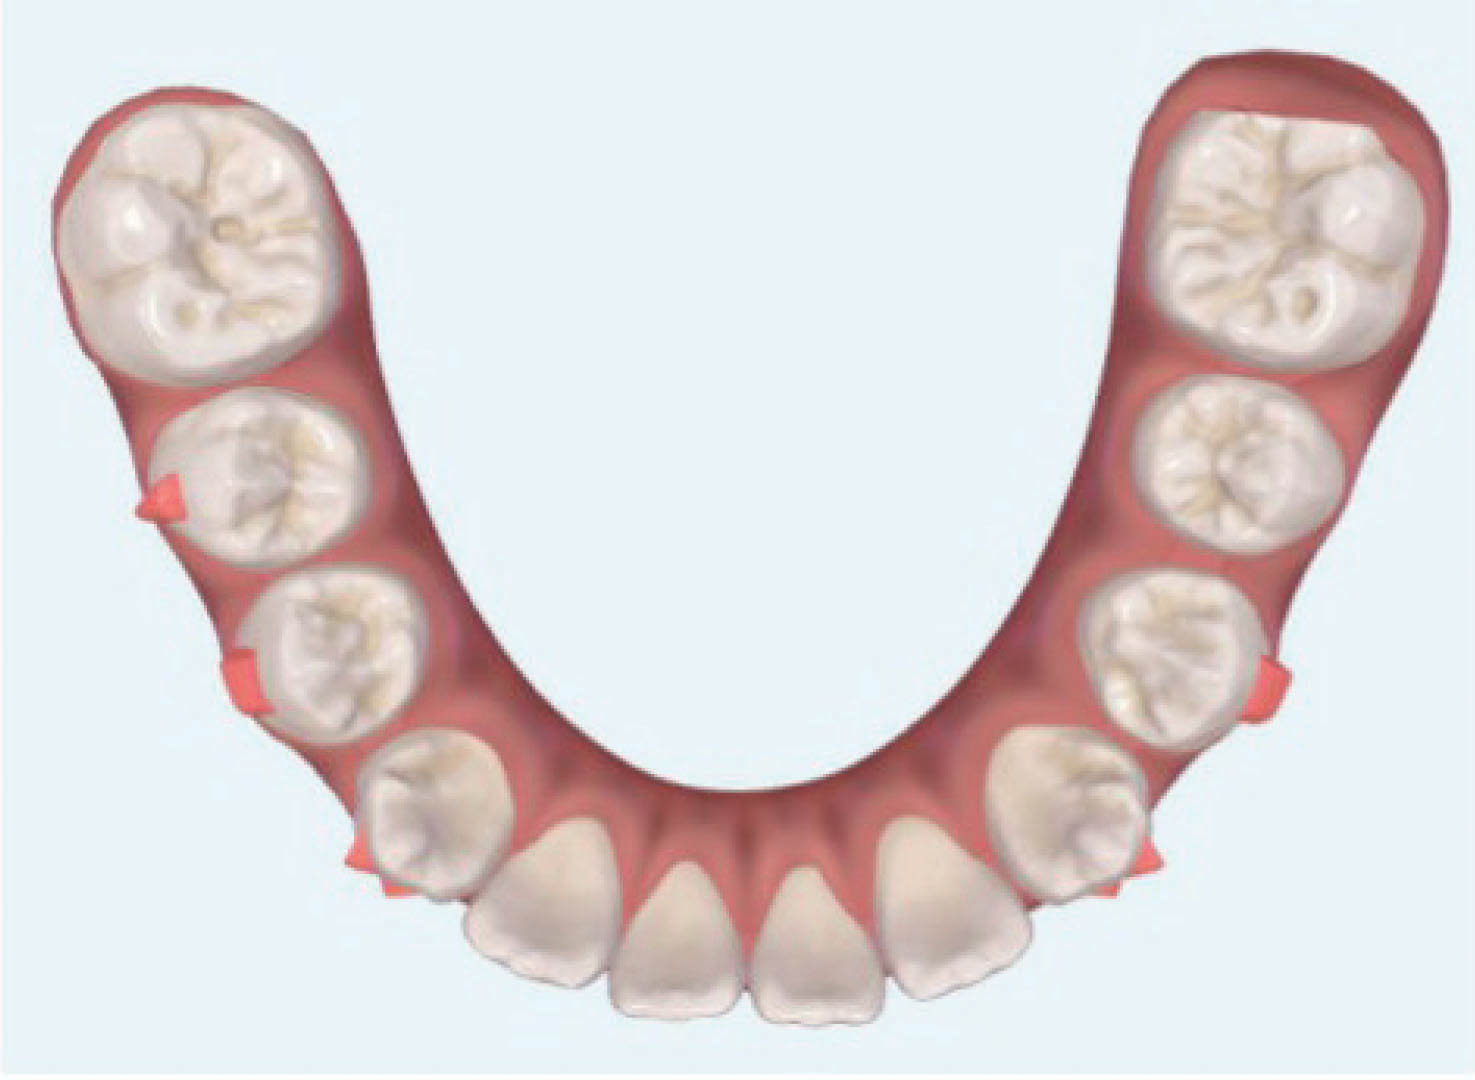

در بیمارانی که انسیزورهای بیرون زده با فضای بین دندانی دارند و آنها را به عقب میبریم احتمال تیپ شدن دندانها حتماً وجود دارد (شکل 41-6 و 42-6).

در بیمار شکل 43-6 و 44-6، انسیزورهای بالا و پایین با تیپ کردن لینگوالی آنها به عقب کشیده شدند تا هم فضا بسته بشود و هم دندانها عمودتر قرار بگیرند.

شکل 41-6